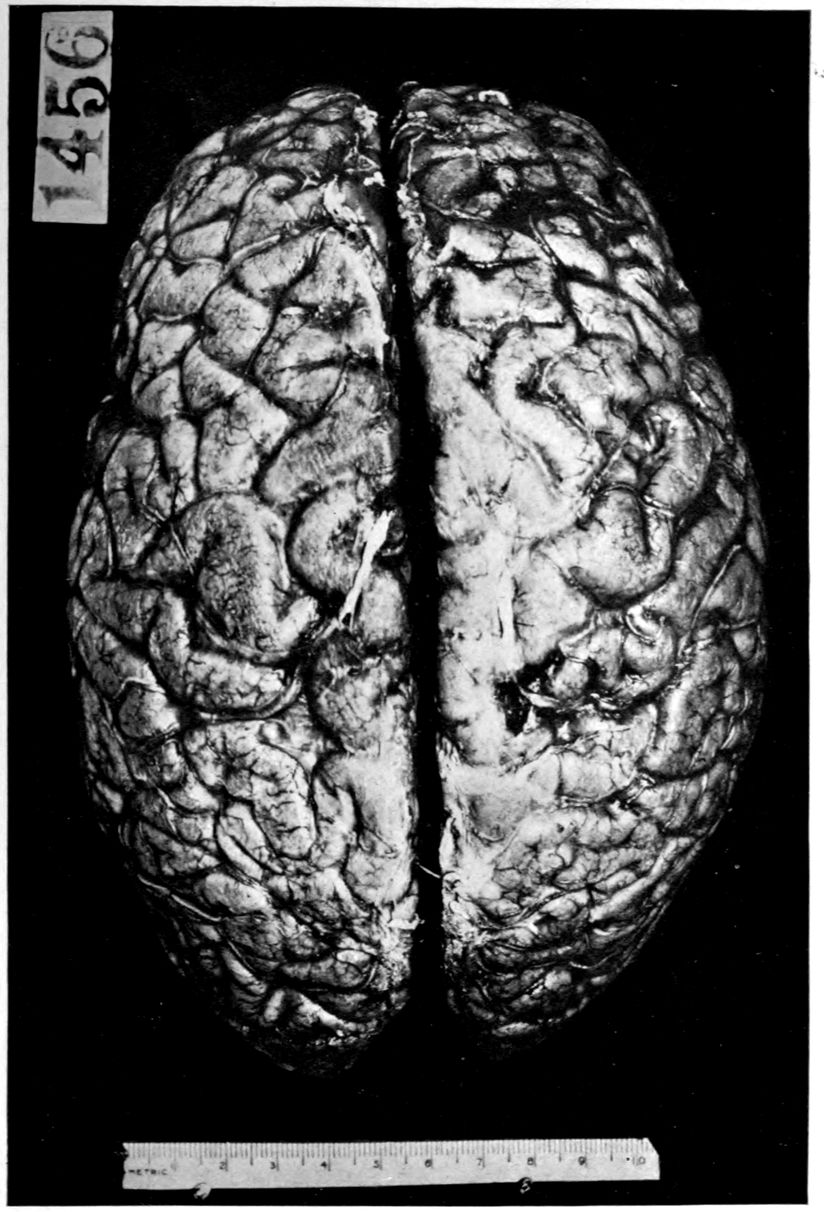

The calvarium was dense and the dura mater thick and adherent. There was a chronic leptomeningitis, which, however, was rather unusual in being most marked in the posterior cisterna and along the sulci of the cerebellar hemispheres. There was a general cerebral sclerosis, with a question of atrophy of the superior temporal gyri (suggesting the so-called Lissauer’s paresis). There was a marked cerebellar sclerosis with a consequent sclerosis (grossly palpable) of the commissural fibres of the pons. There was a generalized slight spinal sclerosis. As a fair sample of the variety of head findings in paretic neurosyphilis, the details of the head examination are presented.

39Crown bald, with a slight fuzzy growth of short hairs. Scalp slightly adherent to calvarium; latter of usual thickness but denser than normal. Dura adherent to calvarium in region of vertex; dura not remarkable. Sinuses normal. Arachnoid villi moderately developed. Pia mater a trifle thickened and rather evenly throughout the cerebral portion. Linear sulcal markings are remarkable for their absence. The wall of the cerebellomedullary cisterna is thick and opaque. The most prominent pial thickenings are over the cerebellum. These are linear or may show feathery out-growths and are seated over the sulci, particularly in the neighborhood of the fissure and about the great cerebellar notch. They correspond fairly well with the focal variation in consistence of underlying tissues noted below.

Brain weight, 1265 grams. Consistence somewhat increased throughout and somewhat evenly increased. The prefrontal region shows the maximal increase of consistence but the remainder of the frontal region and corresponding occipital region are much firmer than normal. The two superior temporal gyri appear to be firmer than adjacent gyri and are possibly slightly diminished in superficial diameter. The hippocampal gyri are fairly firm. The substance on section is a trifle more moist than normal. The gray and white matter cut quite evenly. Diminution in depth of gray matter, if existent, could not be demonstrated. The ventricles show a moderate sanding throughout, best marked in the fourth ventricle. The basal ganglia are not remarkable except for the development of numerous dilated perivascular spaces about the lenticulostriate vessels. The pons is atrophic, but more so on the right side. The pons, like the prefrontal cortex, shows on section a distinct increase of consistence immediately beneath the pia mater. The white bands of the pons on section are distinctly firmer than the intervening substance. The olives are of equal consistence. Weight of cerebellum, pons, and medulla, 155 grams. The cerebellum shows an obvious atrophic and gliotic process of a symmetrical character. The superior surface, including both vermis and hemispheres, shows a consistence above normal and general reduction of the depth measured from the white matter. The reduction in depth gives rise to a visible depression as compared with tissue posterior to the postclival sulci. The lobus cacuminis, though slightly raised from the surrounding lobes, is equally firm, if not firmer. The superior and inferior surfaces show practically an equal increase of consistence. The dentate nuclei are not especially increased in consistence. The flocculi are reduced in size about one-third.

Summary: We here present a case with numerous and widespread neurosyphilitic lesions. However, the gross cerebral vascular complications of Case 1 (Alice Morton) and of Case 2 (Francis Garfield) are notably absent in James Dixon. Rather atypical (there seems to be always something atypical in cases of neurosyphilis!) are the liver lesions and arteritis of the leg, atypical, that is to say, for Paretic Neurosyphilis. Highly typical of paretic neurosyphilis and almost constant therein is the aortic sclerosis.